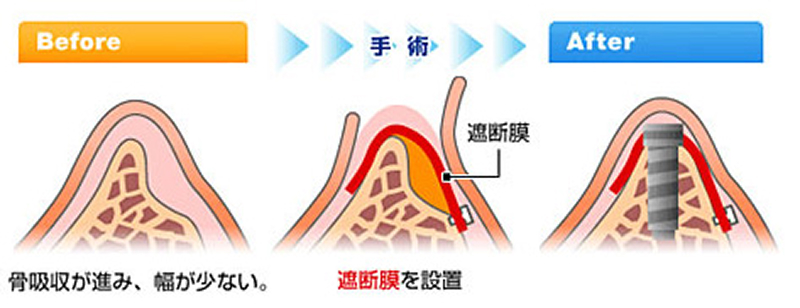

GBR

~骨が少なくてインプラントは無理といわれた患者さんへ~

GBRとはGuided Bone Regenerationの略で『骨を誘導し再生させる』という意味です。

インプラント治療を行う際に骨量が不足した際に用いる骨増大法です。

この骨造成法は歯周病治療の分野ではGTR法(再生療法)として以前から利用されていた方法です。この手法を、インプラント治療へと応用した治療法になります。

- 治療期間

- 6ヶ月~1年

- 治療回数

- 約6回

メリット

- 失われた骨を再生させることで、理想的な位置へのインプラント埋入を可能にします

- インプラントの土台となる骨が強化され、長期的な安定性が格段に向上します

- 歯肉のボリュームも回復するため、審美的に優れた結果に繋がります

デメリット

- 保険対象外となり治療費が高額になる可能性があります

- 症例によっては手術が必要な場合があります

- 症骨が再生し成熟するまでの期間が必要なため、治療期間が長くなる可能性があります

- 症術後、腫れや痛み、軽度の出血などが見られる可能性があります

スプリットクレスト法

~骨が少なくてインプラントは無理といわれた患者さんへ

インプラント手術において一番頻繁に問題となることはインプラントを埋入するのに十分な骨量がないことです。とくに前歯は骨の高さには問題ないですが、幅が不足してることがおおいです。このようなとき骨の頂上部にクサビのような形の特殊な器具を挿入しながら、少しずつ骨幅を広げインプラントの埋入が可能な状態にします。

- 治療期間

- 約6ヶ月

- 治療回数

- 約8回

メリット

- 骨を削る量を最小限に抑えるため、患者さんの身体的な負担を軽減できます

- 骨の幅が3mm程度の症例でも、骨を分割・拡張してインプラントの埋入を可能にします

- 従来法では対応が難しかった、薄い骨の症例にも適用できる可能性があります

デメリット

- 保険対象外となり治療費が高額になる可能性があります

- 骨質が硬い下顎や、隣接歯がある部位など、適用が難しい場合があります

- 骨を正確に分割・制御するには、術者の高度な技術が不可欠です

- 稀に術後の骨吸収が起こる可能性があります